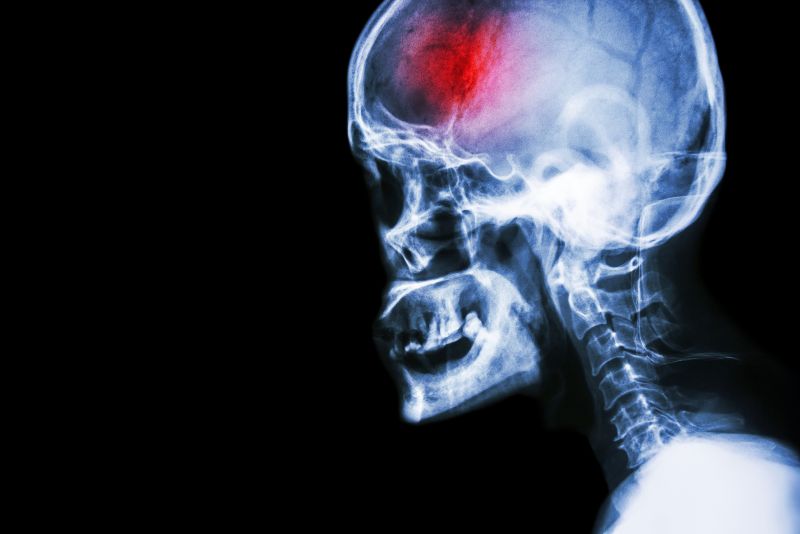

A stroke (previously known as a cerebrovascular accident) when there is a decreased flow of blood to the brain from either a blockage in the blood vessels that supply the brain (ischemic stroke), or a bleed from the blood vessels that supply the brain (hemorrhagic stroke). When the blood flow to the brain is blocked it prevents the brain from getting the needed oxygen and nutrients to function. Without oxygen the brain cells can be permanently damaged or die and the physical and mental functions related to that area of the brain will be affected. A stroke is a medical emergency and rapid treatment is crucial to decreasing the damage caused by a stroke.